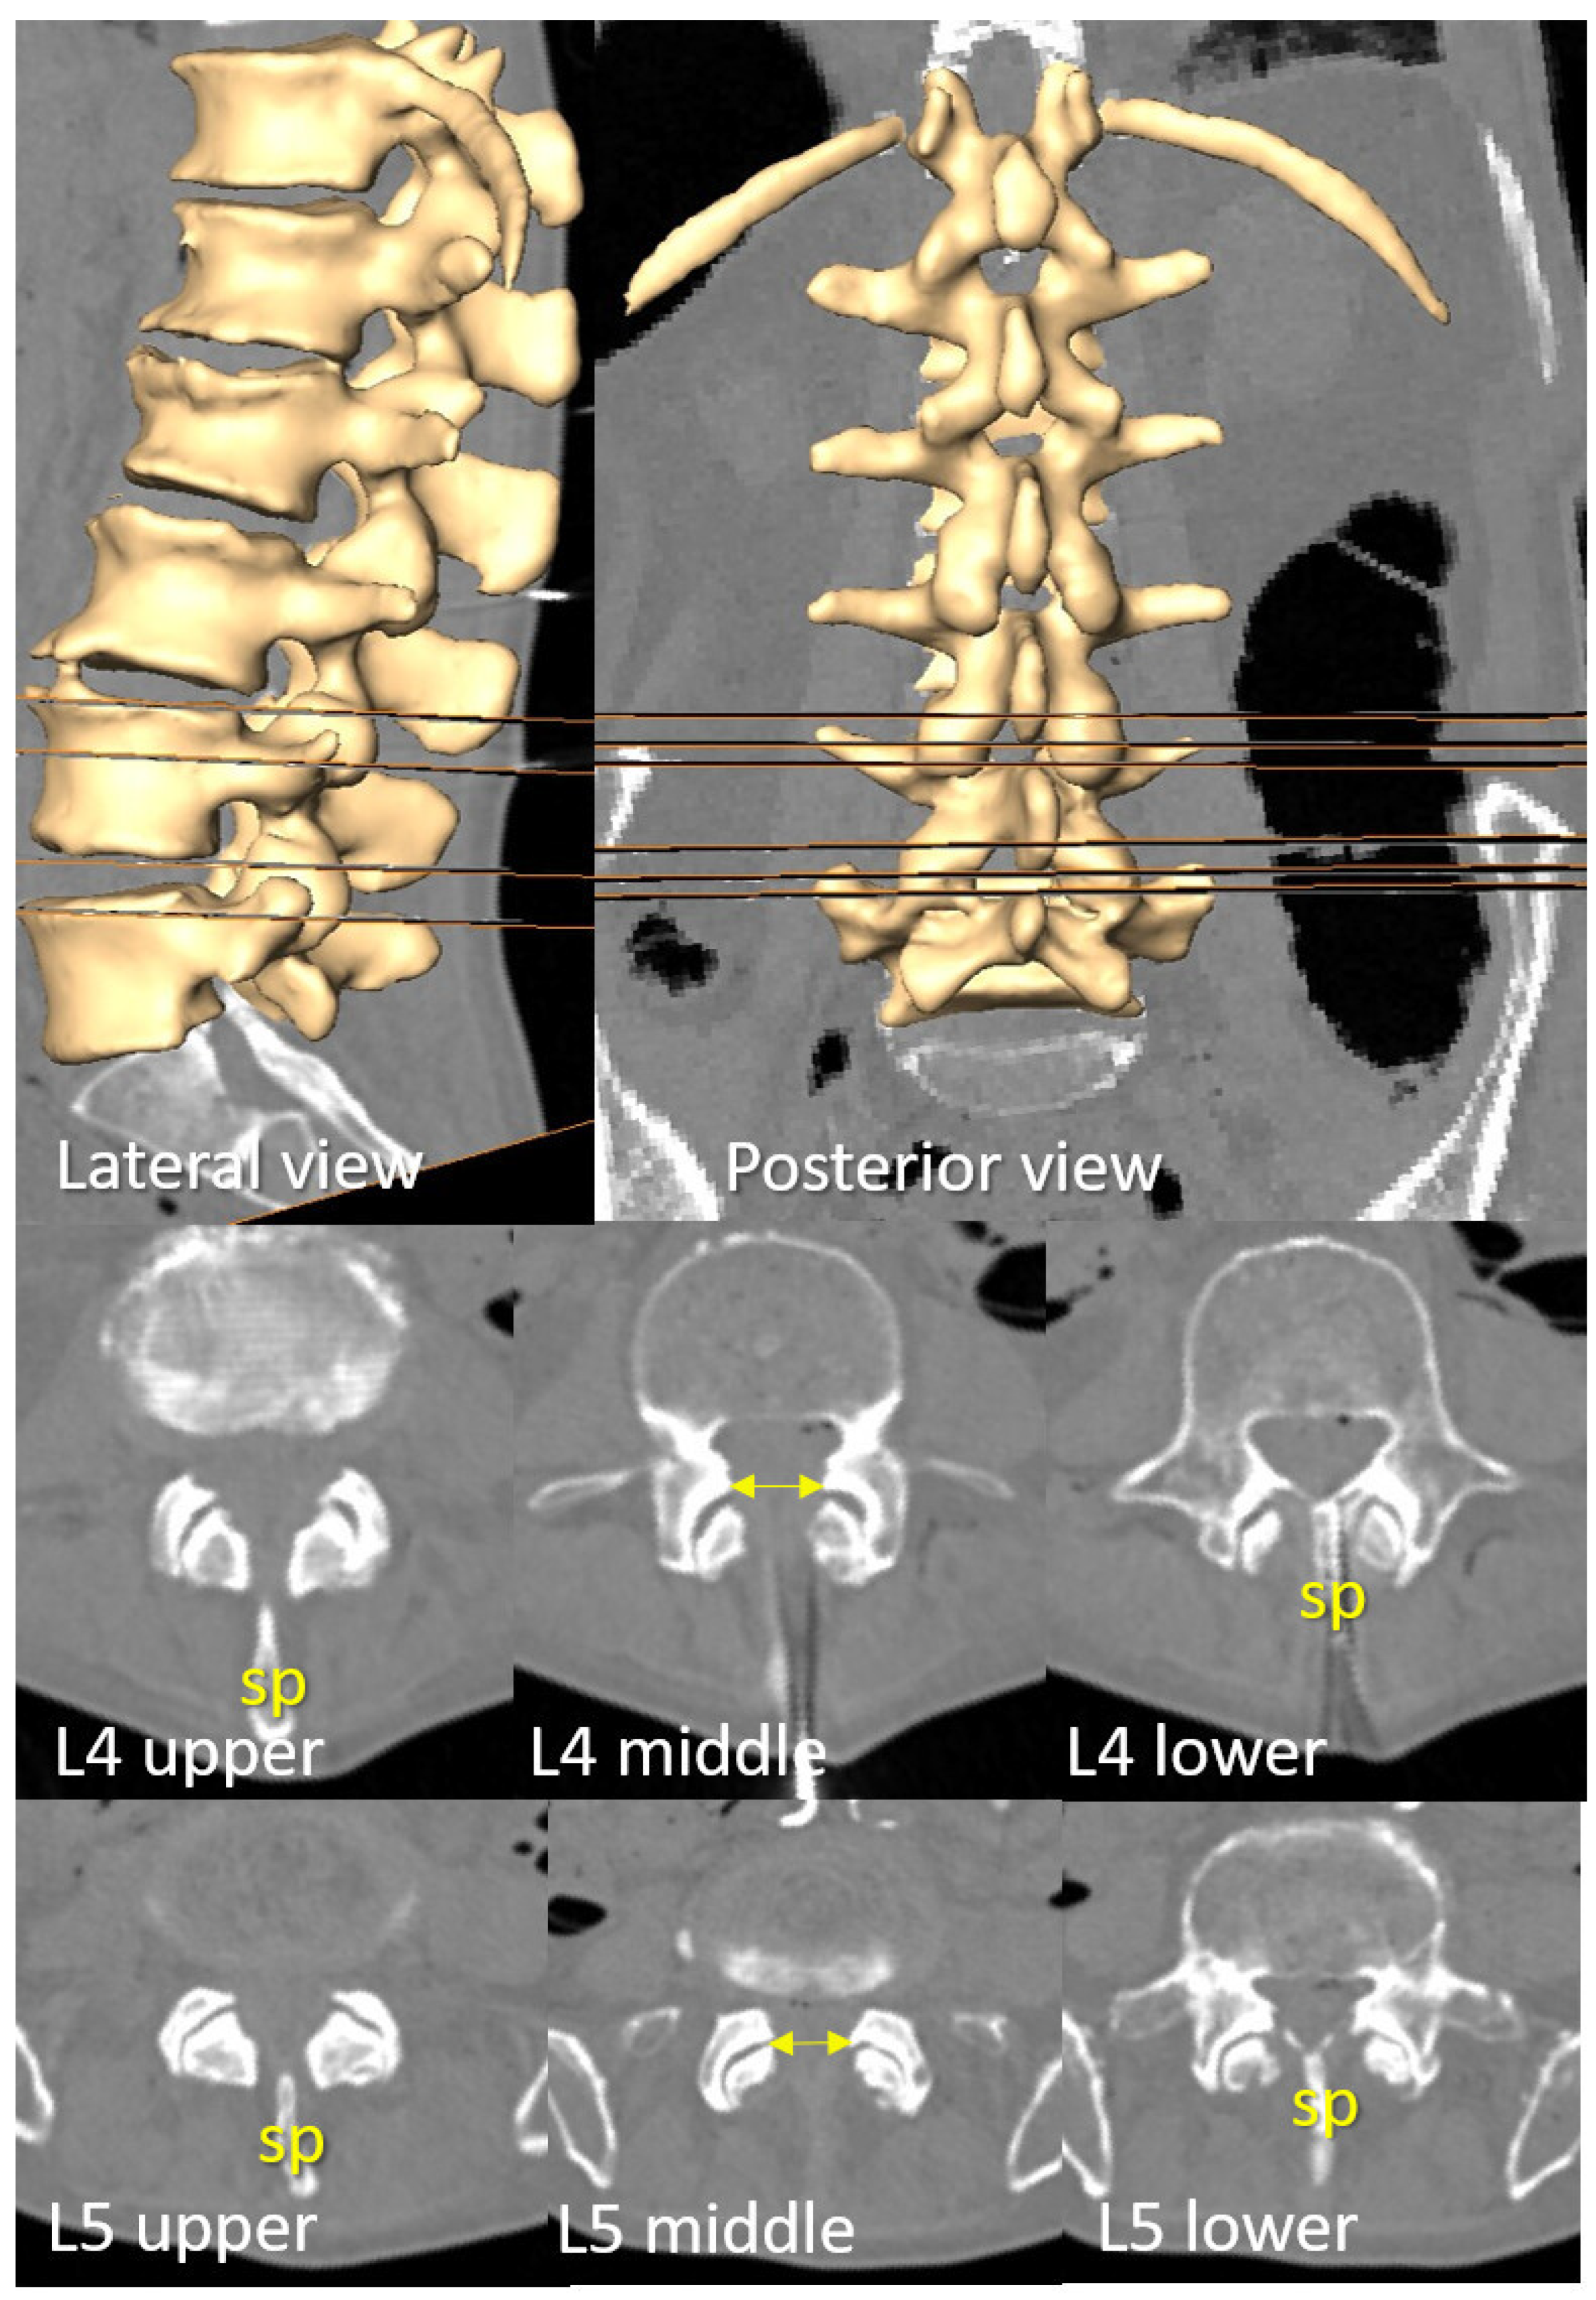

3.2. D Reconstruction, Transverse Process and Interlaminar Window

3.3. Viable or Non-Viable Medial Needle Insertions